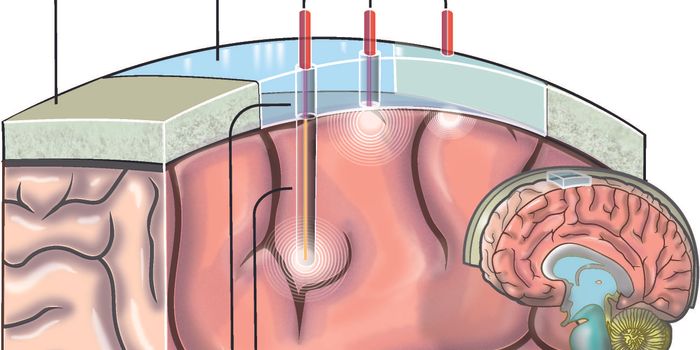

DEC 03, 2020NeuroscienceTo obtain high-resolution images of the brain, researchers usually need to reduce the thickness of the skull or cut into ...